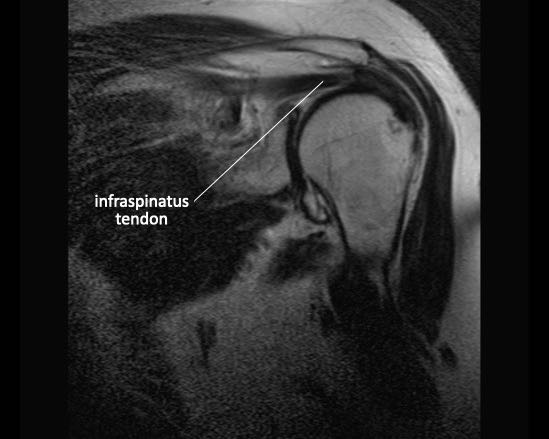

Cơ dưới gai

Cơ dưới gai nằm ở phía sau xương bả vai, phía dưới gai xương bả vai. Gân cơ dưới gai bám vào mặt sau của mấu động lớn.

Cơ dưới gai là cơ xoay ngoài mạnh, đồng thời hỗ trợ cả động tác dạng và khép.